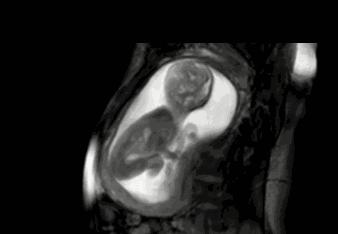

此时孕妈妈是无法感受得到,只有经过B超检查,就可以看得到宝宝的各种动态。